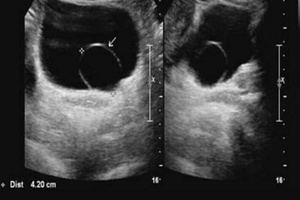

1. Ультрасонография является лучшим первичным этапом диагностики уретероцеле Ультразвуковое исследование назначают в качестве контрольного обследования для оценки внутриутробного развития плода или при диагностике инфекции мочевыводящих путей Эта методика позволяет визуализировать верхние мочевыво-дящие пути и выявить гидронефроз Она также позволяет обнаружить кистозное объемное образование в нижней части дистального отдела мочеточника и в проекции мочевого пузыря